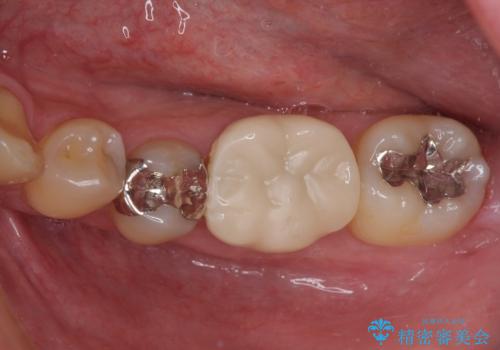

- 保険診療で装着した奥歯の白いクラウンの具合がよくないとのことで来院された患者様です。

保険診療で安価に白いクラウンが入れられるということで選択されたそうですが、装着後に痛みを感じたり、ものが挟まって不快であったりと不便が多いため、セラミッククラウンにて補綴治療を行うこととしました。